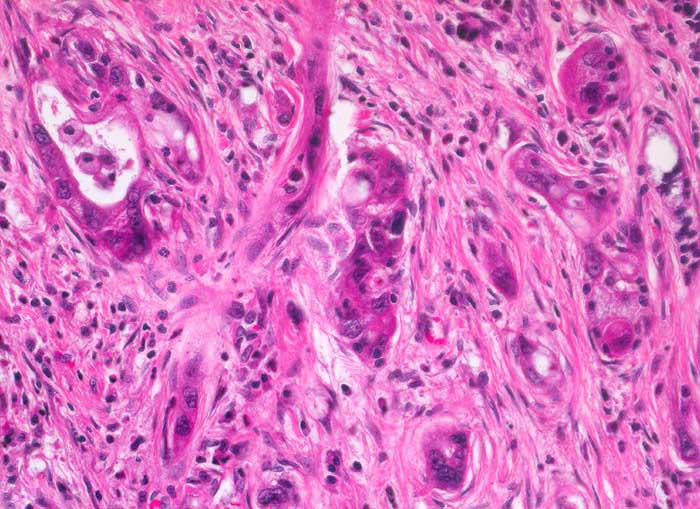

Die meisten Pankreaskarzinome sind mässig bis hoch differenziert und führen zu einer deutlichen desmoplastischen Stromareaktion (derbe Konsistenz). Hochdifferenzierte Tumoren (> 1502) können sehr ähnlich aussehen wie eine chronische Pankreatitis (> 4243). Im Gegensatz zur Pankreatitis sind die neoplastischen Drüsen verformt oder rupturiert und zeigen zelluläre Atypien (grosse polymorphe Kerne mit prominenten Nucleolen). Die Tumordrüsen sind unregelmässig im Stroma angeordnet und nicht lobulär wie in der Pankreatitis. Nicht selten ist eine Nervenscheideninvasion nachweisbar (> 5884). Gelegentlich zeigen die Gänge im tumorfreien Parenchym dysplastische Veränderungen oder der Tumor breitet sich intraduktal entlang des Pankreasganges aus.

• Unregelmässige Anordnung der Drüsen (keine Läppchenarchitektur erkennbar).

• Kribriforme Drüsenformationen.

• Inkomplette Drüsen mit unvollständigen Lumina und Infiltration des Stromas durch Tumoreinzelzellen.

• Nekrotische Tumorzellen in den Drüsenlumina.

• Ausgeprägte Polymorphie und Hyperchromasie der Tumorzellkerne.

• Desmoplastisches Stroma.